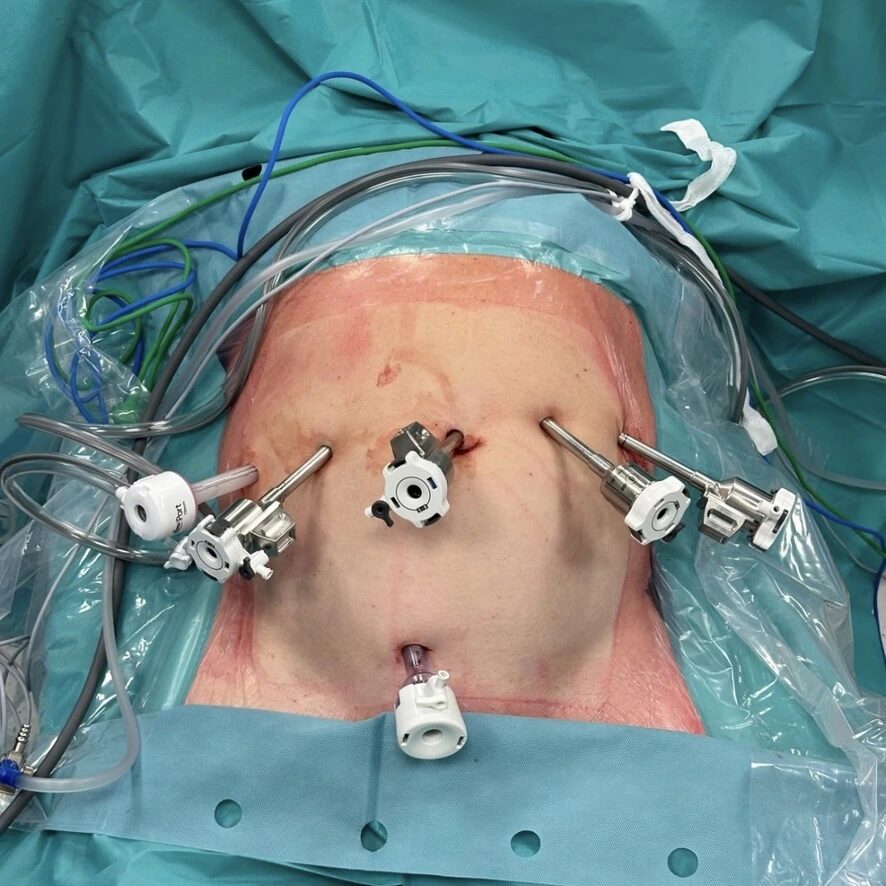

- dispozitivul operator cu brațele robotului daVinci Xi montate;

- Aspectul imediat postoperator, cu incizia transversală suprapubiană utilizată pentru extragerea specimenului chirurgical;